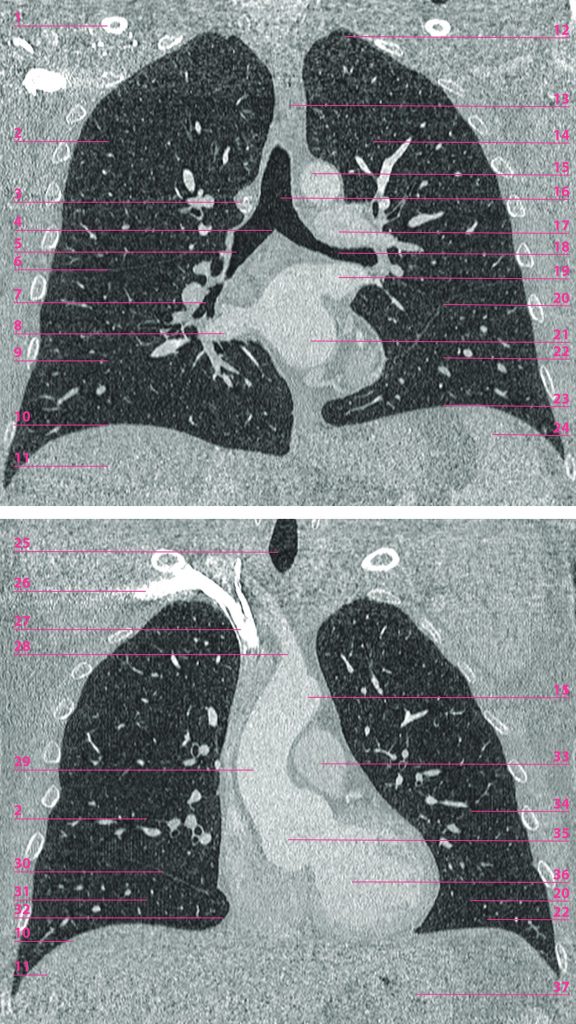

Fig. 89.3 Reconstructions frontales à partir d’une acquisition tomodensitométrique après injection de produit de contraste.

1. Clavicule droite. 2. Lobe supérieur du poumon droit. 3. Crosse de la veine azygos. 4. Carène. 5. Bronche principale droite. 6. Grande scissure. 7. Tronc de la pyramide basale droite. 8. Veine pulmonaire inférieure droite. 9. Lobe inférieur du poumon droit (pyramide basale). 10. Coupole diaphragmatique droite. 11. Dôme hépatique (segment VIII). 12. Apex pulmonaire gauche (au-dessus de la 1re côte). 13. Partie thoracique de l’œsophage. 14. Lobe supérieur du poumon gauche (culmen). 15. Arc aortique (segment 2). 16. Partie thoracique de la trachée. 17. Artère pulmonaire gauche. 18. Bronche principale gauche. 19. Veine pulmonaire supérieure gauche. 20. Grande scissure gauche. 21. Atrium gauche. 22. Lobe inférieur du poumon gauche (pyramide basale). 23. Coupole diaphragmatique gauche. 24. Rate. 25. Partie cervicale de la trachée. 26. Veine subclavière droite (opacifiée par le produit de contraste). 27. Veine brachiocéphalique droite. 28. Tronc brachiocéphalique. 29. Aorte ascendante (segment 1). 30. Petite scissure. 31. Lobe moyen du poumon droit. 32. Angle cardiophrénique droit. 33. Tronc pulmonaire. 34. Lobe supérieur du poumon gauche (lingula). 35. Sinus aortique (segment 0). 36. Ventricule gauche. 37. Estomac (fundus).

Source : CERF, CNEBMN, 2022.